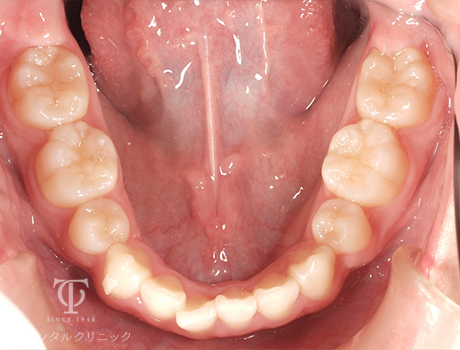

マウスピース装着前

Case01

-

- 症状

- 前歯の歯並びがずれてきた

- 治療期間

- 約5か月

- 治療費用

- 330,000円

以前全顎矯正をしていて後戻りをおこしてしまった患者様です。軽度の叢生のため、マウスピース矯正をおこないました。